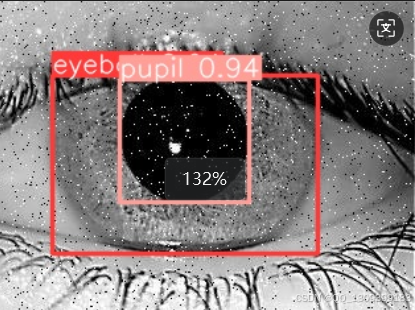

model = YOLO(r"best.pt")

model.predict(source=r"73.jpg",

save=True )

4. 直径计算

几何测量

一旦模型能够准确地定位瞳孔和眼球,就可以基于预测结果计算其直径。对于圆形物体来说,可以直接测量两个最远点之间的距离;对于非标准形状,则可能需要用椭圆拟合或者其他数学方法来估算。

校准

考虑到摄像头的不同焦距和拍摄距离可能导致尺寸失真,因此建议进行适当的校准工作,以保证测量值的准确性。